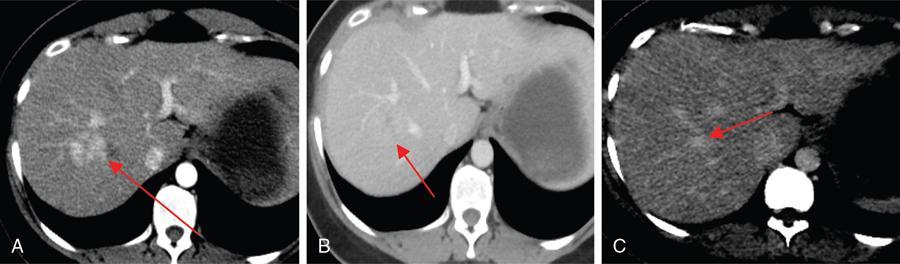

Ritu K. Kashikar, Shrinivas B. Desai, Pooja Punjani Vyas, Nilesh Doctor, Vivek Shetty Owing to advances in technology, focal liver lesions (FLLs) are increasingly encountered. Imaging particularly computed tomography (CT) and magnetic resonance imaging (MRI) play a vital role in diagnosis and characterization of FLL, thus avoiding unnecessary biopsies and interventions. Multiphase CT accurately diagnosis most liver lesions. Better soft tissue contrast and lack of ionizing radiation makes MRI a preferred modality in diagnosing FLLs. MRI with or without contrast for characterization of liver lesions regardless of preexisting liver disease has been assigned the highest rating as per American College of Radiology Appropriateness Criteria (Table 9.11.1). Solid lesions of epithelial origin Solid lesions of nonepithelial origin Pitfalls Cystic liver lesion Developmental cyst Infective cyst Miscellaneous Tmours of hepatocellular origin Tumours of nonepithelial origin Malignant cystic lesion Hepatic metastasis Ultrasound is often the initial modality for diagnosis and also the incidental detection of FLLs. Limitations to USG include the detection of small lesions less than 2 cm in size, particularly in patients who are cirrhotic or undergoing chemotherapy. Characterization of FLLs, involvement of crucial structures such as blood vessels, local staging and decisions such as operability are also not accurate with ultrasound alone and require confirmation with CT/MRI. The liver typically images in supine and left lateral positions. A curvilinear transducer with a frequency of 1.5 Hz is used. The subcostal diagonal, subcostal longitudinal or sagittal and transverse right intercostal lateral views are used. Right lobe of liver is imaged through an intercostal approach when the patient is taking deep inspiration. Subcostal view is used to image the three hepatic veins in one view. Transverse, longitudinal and oblique views of the liver are taken to image all the segments of liver. Colour and power Doppler have increased sensitivity for FLL detection, but sensitivity is still inferior to contrast-enhanced CT and MRI. The introduction of microbubble contrast agents (CAs) and the development of contrast-specific techniques have opened new perspectives in ultrasound of the liver. The technique is based on a new class of intravascular microbubble agents which contain perfluoro gases instead of air. This when combined with scanning modes sensitive to harmonic responses of microbubbles enable tissue signal suppression. The advent of the multislice technique and isotropic voxel have improved the spatial resolution of CT, allowing the recognition of small FLLs in difficult areas. Multislice CT has a sensitivity and specificity in the diagnosis of malignant FLLs of 63% and 64%, and 92 and 97%, respectively. Contrast media administration with dose based on the patient’s weight (approximately 600 mg iodine/kg of bodyweight), an iodine content of 350–400 mg/mL and a high injection rate of 4–5 mL/s are imperative to attain good contrast enhancement. Region of interest in the abdominal aorta and a threshold of 100 HU allows correct timing for threshold. A delay of approximately 18 s after the threshold provides the first arterial phase, allowing detection of hypervascular FLLs such as hepatocellular carcinoma (HCC). The late arterial phase is obtained approximately 10 s after the early arterial phase and shows progressive enhancement of hypervascular lesions, improving detection rate, while the optimal hepatic enhancement in the portal phase is reached approximately 50–60 s after the threshold. Portal venous thrombi are also best detected in this phase. The venous phase aids in the detection of washout, hepatic venous thrombosis. Delayed phase is often required in lesions such as cholangiocarcinoma and haemangioma, which show progressive enhancement (Table 9.11.2, Fig. 9.11.1). Delayed phase images are required for tumours such as cholangiocarcinoma and large haemangiomas, which reveal delayed enhancement. As mentioned previously, MRI is the modality of choice in diagnosis of FLLs. Most FLLs appear hyperintense on T2W1 images with varying intensity depending upon the water content and flow dynamics. FLLs are typically hypointense on T1W1 images with the exception of fat containing, haemorrhagic lesions and those containing chelates of metals like regenerating/dysplastic nodules. In- and opposed-phase images help in detection of intralesional fat. Diffusion-weighted images are beneficial particularly in noncirrhotic population and best suited in detection of metastasis. Postcontrast images obtained with extracellular agents are parallel to those obtained with CT (Fig. 9.11.2). The pre- and postcontrast MRI protocol is mentioned in Table 9.11.3. T2-weighted single-shot fast spin-echo (SE) T1-weighted in- and opposed-phase GRE Dynamic 3D T1-weighted FS spoiled GRE (in hepatic arterial, portal venous and equilibrium phases) There are two main categories of CAs used in liver imaging – the extracellular and the hepatocyte-specific (Fig. 9.11.3). Extracellular agents are more widely used and provide information similar to contrast-enhanced CT study. The advantage of the other category of CAs, that is, hepatocyte-specific agents, is the ability to provide this extracellular information with added benefit of delayed phase information. Tumours of hepatocellular origin with functioning hepatocytes take up and biliary excretion with take up and retain these agents appearing isointense to background liver. Lesions without functioning hepatocytes fail to retain contrast and hence appear hypointense to background liver on delayed phase. This allows better detection and characterization of focal liver lesion particularly those lesser than 2 cm (Table 9.11.4). Haemangioma is the most common benign hepatic tumour. The incidence in general population varies from 1% to 20%. Females have a higher preponderance with variable female to male ratios of 2:1 to 5:1. Imaging in particular MRI has high reliability in diagnosing classic haemangioma. The sensitivity and specificity of MRI is greater than 90% in diagnosis. The aetiology of haemangioma is unknown. Since haemangiomas are known to run in families, a genetic origin has been implicated, while other mesenchymal tumours are thought to be congenital. Most patients are asymptomatic and often the lesion is discovered as an incidental finding. Pain in the right upper abdomen is the most common complaint; others include loss of appetite, nausea, vomiting and abdominal discomfort. Symptoms are usually seen in large haemangiomas or those with complications. Liver function tests and tumour markers like AFP and CA19.9 are within normal limits. Blood-filled cavities of varying sizes lined by flat endothelial cells and supported by fibrous connective tissue are seen on histology. Three histological subtypes have been described: the capillary haemangioma, the cavernous haemangioma and the sclerosing haemangioma. The imaging features of a haemangioma depend on its size; typical haemangiomas are mostly less than 3 cm in diameter. Haemangiomas are hyperechogenic, homogeneous lesion presenting a posterior acoustic enhancement (Fig. 9.11.3). The hyperechogenicity of haemangiomas is related to the interfaces between vascular spaces, fibrous stroma and the slow blood flow. Typically, haemangiomas have slow flow and hence do not show vascularity on colour or power Doppler. The sensitivity and specificity of ultrasound in differentiating haemangioma from other malignant lesions are high, with values of approximately 94.1% and 80%, respectively, for lesions less than 3 cm in diameter. Unlike HCC, no flow is seen on colour Doppler. A peripheral echogenic rim around hypoechoic lesions can suggest haemangioma. On the contrary, perilesional hypoechoic rim called the target sign is seen in lesions such as metastasis (Table 9.11.5). Adenomas can be distinguished on the basis of the absence of posterior acoustic enhancement and characteristic pattern of peripheral vascularity seen in adenoma. Another differential diagnosis to be considered is focal nodular hyperplasia (FNH), which has the characteristic ‘spoke-wheel sign’. Contrast-enhanced ultrasound (CEUS) improves specificity for the diagnosis of haemangioma. The vascularity pattern with contrast-enhanced USG is similar to that seen with CT. The typical hemangioma (HH) shows peripheral nodular enhancement in the arterial phase with complete (but sometimes incomplete) centripetal filling in the portal venous and late phases. This particular pattern of enhancement helps in differentiating haemangiomas from other lesions like adenomas, FNH, HCC or metastasis. This characteristic enhancement pattern has a sensitivity of 98% for histologically proven HH. One should be aware that an HH can rarely have a centrifugal enhancement. Computed tomographic (CT) findings consist of a hypoattenuating lesion on nonenhanced images. Haemangiomas show peripheral discontinuous nodular enhancement on arterial phase of dynamic contrast-enhanced CT. The density of the nodules is equivalent to that of the aorta. Centripetal filling with is seen on venous phase, which progresses to uniform enhancement. The enhancement persists on delayed phase (Fig. 9.11.4). Washout of contrast on delayed phase is not seen in haemangioma and if seen, alternate diagnosis must be considered. This classical pattern of enhancement cannot be highlighted in very small lesions of less than 5 mm, which can be difficult to characterize. In patients with severe fatty infiltration of the liver, HH can appear hyperdense relative to the adjacent liver parenchyma on nonenhanced scan. Haemangiomas are hyperintense on T2-weighted images, which is identical to that of cerebrospinal fluid. T2 hyperintense signal is classically described as ‘light bulb bright’. Malignant lesions of the liver do not appear as bright on T2W1 images. They appear hypointense to adjacent liver on T1-weighted images. Long relaxation T2W1 images further improve accuracy in diagnosis of haemangiomas and help in differentiation from metastasis. Haemangiomas, unlike other liver lesions retain hyperintense signal on long relaxation T2W1 images. A threshold of 112 ms has 92% accuracy, 96% sensitivity and 87% specificity for differentiating haemangiomas from metastasis. On gadolinium administration, the enhancement pattern is similar to that seen with iodinated contrast on CT. Classic enhancement pattern in combination with characteristic T2 appearance are diagnostic for haemangioma (Fig. 9.11.5). Certain pitfalls exist in diagnosing haemangiomas using gadoxetate disodium. Due to the lack of hepatocytes, haemangiomas appear hypointense to the background liver on delayed hepatocyte phase and mimicking malignant process (Table 9.11.6). Lesions shown peripheral nodular arterial enhancement (Table 9.11.7): On fluorodeoxyglucose-positron emission tomography (FDG-PET)/CT, most hepatic haemangiomas appear low-attenuation lesions with FDG avidity equal to background liver parenchyma and are easily determined to be benign. However, a small percentage of haemangiomas may be FDG-avid. If an FDG-avid hepatic lesion demonstrates the characteristic enhancement pattern, this is consistent with an FDG-avid haemangioma. Technetium-99m pertechnetate-labelled red blood cell scintigraphy has high specificity in the diagnosis of haemangiomas. In this technique, there is decreased activity in haemangiomas on early images and increased activity on delayed blood pool images. Therefore, radionuclide scintigraphy has a sensitivity of 78% and an accuracy of 80% and may be a valuable tool when the diagnosis cannot be achieved with other imaging modalities. Large haemangiomas are often heterogeneous with internal clefts and septae. They are termed as giant haemangiomas when they exceed 4 cm in diameter. Discrepancies are there in definition with some authors defining giant haemangiomas as lesions greater than 6 cm or 12 cm in diameter. These may cause symptoms of abdominal pain and distension. These haemangiomas demonstrate changes such as haemorrhage, thrombosis, extensive hyalinization, liquefaction and fibrosis. The central cleft-like area may be due to cystic degeneration or liquefaction. On USG, they reveal heterogeneous echotexture. They are hypoattenuating and heterogeneous on nonenhanced CT with central areas of low attenuation. After intravenous administration of contrast material, the typical early, peripheral and globular enhancement is observed. These may show irregular or ‘flame-shaped’ discontinuous peripheral enhancement as opposed to typical nodular enhancement pattern seen in smaller haemangiomas. Although centripetal pattern of enhancement is seen during the venous and delayed phases, the filling-in incomplete. Central scars are defined in this subset of haemangiomas (Fig. 9.11.6). At MRI, T2-weighted images show a markedly hyperintense cleft-like area and some hypointense internal septa within a hyperintense mass. On delayed phase, incomplete filling and central scar are seen similar to CT (Fig. 9.11.7). Complications include intratumoural haemorrhage, inflammatory changes or consumptive coagulopathy (Kasabach–Merritt syndrome). These may warrant management such as arterial embolization or resection. This pattern is seen 16% of all haemangiomas, and is seen more often in small haemangiomas (42% of haemangiomas) <1 cm in diameter. CT and MRI show immediate homogeneous enhancement at arterial phase CT or contrast-enhanced MRI. The size of the blood spaces is the reason for difference in enhancement pattern. Smaller the lesion, smaller the size of blood spaces and faster the rate of spread of contrast material. These lesions usually show perilesional halo of hyperenhancement on the late arterial phase, which is believed to be due to arteriovenous shunting. Rapid arterial enhancement makes these haemangiomas difficult to distinguish from hypervascular metastasis (Table 9.11.8). However, washout of contrast is seen from haemangiomas on delayed phase (Fig. 9.11.8). Hepatic haemangiomas rarely demonstrate calcifications, while haemangiomas in other locations frequently demonstrate phleboliths. Calcified haemangiomas are mostly found incidentally. Calcifications may occur in the marginal or central portion of the lesion and consists of multiple spotty calcifications, which correspond to phleboliths. However, large, organized calcifications are also possible. Some calcified haemangiomas may demonstrate poor enhancement. Hyalinized hepatic haemangiomas are rare. It has been suggested that hyalinization represents an end stage of haemangioma evolution. These haemangiomas are usually asymptomatic. The radiological features of a haemangioma are completely altered ones hyalinization occurs; hence biopsy is often mandatory for diagnosis. Hyalinized haemangiomas show only slight high signal intensity on T2W1 images. There is lack of early enhancement on dynamic contrast-enhanced images (Fig. 9.11.9). Fluid–fluid levels within haemangiomas are very rare. Fluid–fluid levels are seen both with CT and MRI with inferior layer representing the red blood cells and superior layer unclotted serous blood. Dependent hyperdensity/T1 hyperintensities can be seen corresponding with dependent haemorrhage. Pedunculated haemangiomas are very rare. They can be asymptomatic or complicated by subacute torsion and infarction. Typical enhancement pattern and signal on T1 and T2W1 images are clues to the diagnosis. Capsular retraction is usually associated with malignant tumours such as cholangiocarcinoma, epithelioid haemangioendothelioma or metastases. Rarely, it has been seen in haemangiomas. A possible mechanism could be fibrous degeneration. Multiple haemangiomas are seen in 10% of cases and usually show classical imaging features. Fatty infiltration of liver may alter the imaging appearances of lesions. Haemangiomas appear slightly hyperechoic, isoechoic or hypoechoic relative to the fatty liver. At nonenhanced CT, the lesion may be hyperattenuating relative to the liver. Contrast-enhanced CT shows peripheral enhancement and delayed filling, an appearance similar to that of a haemangioma in a normal liver. Haemangiomas are less common in setting of cirrhosis and may be difficult to diagnose due to sclerosis. Complications are seen in 4.5%–19.7% and often seen in large lesions such as inflammation, coagulation within can lead to systemic disorders, haemorrhage would lead to haemoperitoneum, volvulus and adjacent organ compression. Irrespective of the size, treatment is indicated only for haemangiomas with significant symptoms, those developing complications, or when there is an inability to exclude malignancy. Attempt should be made to exclude other causes of the patient’s symptoms. The term focal nodular hyperplasia (FNH) was introduced in 1958 by Edmondson. In 1995, the International Working Party classified FNH with other regenerative lesions, and not a neoplastic lesion. It is defined as a nodule consisting of normal appearing hepatocytes occurring in a histologically normal liver. It is the second most common tumour of the liver after haemangioma with a reported prevalence of 0.9%. The lesion is more commonly seen in females with female to male ratio of 8:1. Multiplicity is seen in 20% of patients. The combination of multiple FNH lesions and haemangiomas is considered to be multiple FNH syndrome. Vascular malformation and vascular injury have been suggested as the underlying mechanism. An association with steroids has been denied more recently. FNH has been classified as classic and nonclassic varieties. These have been discussed in Table 9.11.9. Classic FNH is characterized by abnormal nodular architecture, malformed vessels and cholangiolar proliferation. Nonclassic FNH lesions lack one of the following classic features – nodular abnormal architecture or malformed vessels – but always show bile ductular proliferation. Classic FNH on gross appearance shows lobulated contours with multiple nodules surrounded by fibrous septae originating from a central scar, which contains a vascular malformation. On histopathology, nodular hyperplastic parenchyma is seen in classic FNH. Circular or short fibrous septae surround these nodules completely or incompletely. Thickening of the hepatic plates is seen. Fibrous connective tissue, cholangiolar proliferation with surrounding inflammatory infiltrates and malformed arteries, capillaries, vascular channels of undetermined type and veins are seen in the central scar. The arterial blood in FNH shows centrifugal distribution from anomalous central arteries. Fatty infiltration is seen in approximately 50% of lesions, while signs of hepatic steatosis are seen in approximately 20% of cases with classic FNH. Variable amounts of Kupffer cells are seen in both classic and nonclassic variants. Nonclassic FNH is heterogeneous and on gross appearance resembles adenomas in most cases, with vaguely lobulated contours and lack of a macroscopic central scar. The histology varies with subtypes. Subtypes of nonclassic FNH include telangiectatic type, mixed hyperplastic and adenomatous forms and FNH with cytologic atypia. The histological features of these are described in Table 9.11.10. At US, typical FNH is often not well visualized. The lesions may be slightly hypoechoic, isoechoic or slightly hyperechoic. The compressed liver tissue form a hypoechoic halo around the lesion, which appears more prominent in patients with fatty infiltration. A prominent central scar may improve the conspicuity of the lesions. Use of colour and power Doppler US shows vascularity in suspected FNH. On contrast-enhanced USG, FNH is hyperenhancing in the arterial and portal venous phases in more than 90% of cases. The arterial enhancement patterns include central (60%–70% of cases) or eccentric (<20% of cases) with centrifugal filling, but sometimes are homogeneous. Multiphase CT is an excellent modality for detection and characterization of FNH. These lesions classically show a lobulated contour. At unenhanced CT, the lesions are either hypoattenuating or isoattenuating to the surrounding liver. In the arterial phase, the lesions show homogeneous intense enhancement except the central scar and fibrous septa. In the portal and later phases, the lesions become more isoattenuating with the surrounding liver. The central scar reveals enhancement on delayed phase (Fig. 9.11.10). This feature helps distinguish from other lesions with central scar-like fibrolamellar carcinoma. A vascular malformation can be seen in the central scar in some cases (Fig. 9.11.11). There may be enlarged hepatic veins in the vicinity of the mass. FNH do not have portal venous drainage. The drainage is essentially into hepatic venules, hence the enlarged adjacent veins. The central scar is often not identified in small FNH lesions. In a study, 80% of FNH lesions less than 3 cm lacked visible central scar. The sensitivity and specificity of MRI in diagnosis of FNH are 70% and 98%, respectively. The central scar is more often detected with MRI than with CT (78% and 60%, respectively). FNH is typically iso- or hypointense on T1-weighted images (94%–100%) and is slightly hyperintense or isointense on T2-weighted images (94%–100%). The lesions may not be very conspicuous on T2W1 images. The central scar is hyperintense on T2-weighted images in 84% of cases. FNH shows intense homogeneous enhancement in the arterial phase. The enhancement pattern in arterial phase may be nodular, resembling a popcorn, the result of intralesional fibrous septae. Mosaic pattern of heterogeneous enhancement seen in malignant lesions is not seen in FNH. Central vascular malformation may be seen in early phases. These lesions classically fade to isointensity on delayed phase with the exception of the central scar (Fig. 9.11.12). FNH may show a pseudocapsule, which results from compression of the surrounding liver parenchyma by the FNH, perilesional vessels and inflammatory reaction. The pseudocapsule may show enhancement on delayed contrast-enhanced images. A central scar is present at imaging in most patients with FNH. The central scar is hyperintense on T2W1 and hypointense on T1W1 images. The presence of inflammation and vessels within the scar are responsible for the hyperintense signal (Fig. 9.11.13). The scar does not enhance on early phases of contrast study and shows enhancement on delayed phases of dynamic study. The scar is absent in 30% of cases. The hepatocyte-specific CA gadoxetate disodium can be useful in distinguishing FNH from other lesions like adenomas. Densely packed functioning hepatocytes and abnormal blind-ending bile ductules in FNH result in contrast retention and delayed biliary excretion. FNH often shows enhancement on delayed images using gadoxetate disodium, and along with radiating fibrous septae, it may result in a characteristic spoke-wheel appearance. On the contrary, hepatocellular adenomas (HCAs) are usually hypointense to liver on hepatocyte phase images because they lack bile ductules. Superparamagnetic iron oxide (SPIO) is a negative reticuloendothelial-specific CA taken up primarily by the hepatosplenic Kupffer cells. This agent shortens T2 relaxation time predominantly, leading to a significant decrease of SI of normal hepatic. FNH contains Kupffer cells and hence shows significant signal drop after administering SPIO. This CA is, however, not commonly used particularly with advent and increased usage of hepatocyte-specific agents (Table 9.11.11). These lesions have high signal intensity on T2-weighted images, a central scar with low signal intensity on T2-weighted images, a prominent pseudocapsule and incomplete intense enhancement of the lesion. Extreme heterogeneity can be seen in these lesions leading to difficulty in distinguishing from malignant lesions such as HCC and cholangiocarcinoma. Biopsy and histopathology diagnosis are often needed in this subset. Telangiectatic FNH may show areas of haemorrhage. A French study has reported an association of 23% between FNH and haemangiomas. The incidence of coexistence of FNH and adenoma is lower (3.6%). There have also been reports of rare associations of FNH with other types of vascular anomalies like congenital absence of the portal vein, inflammatory pseudotumours of the liver, hepatic vein thrombosis and intrahepatic arteriovenous shunting. Imaging differentials include HCA and other lesions with central scar like fibrolamellar carcinoma, HCC and giant haemangiomas (Table 9.11.12). FNH shows intense arterial phase enhancement and isodensity/isointensity on delayed phase, this feature helps in distinguishing from adenoma, which usually are hypoattenuating on the delayed phase. T1 hyperintensity seen in adenomas is not seen on FNH. Biopsy is recommended in cases where radiological features are atypical and distinguishing from malignant lesions like HCC cannot be made on the basis of imaging findings alone. As there is no risk of malignant transformation and complications are rare, FNH does not need treatment. Patients with large FNH causing compression of adjacent organs or occurrence of torsion in a pedunculated FNH may need surgical resection. Also, patients with diagnostic dilemma may be considered as surgical candidates. Adenoma is a less common benign primary neoplasm of the liver. Women of childbearing age taking oral contraceptives are considered at highest risk; however, it can occur in other women as well as men. Hepatic adenomas (HAs) were particularly associated with the use of older generation of OC pills with high-oestrogen content. Adenomas have also been reported to occur in men secondary to anabolic steroid/androgen use. Clomiphene, danazol and testosterone in patients with Fanconi anaemia (FA) and without FA, Klinefelter’s syndrome, glycogen storage disorders (GSDs) I, III and IV, alcohol and metabolic syndrome are other hormonal therapies and conditions associated with adenoma. Development of >10 adenomas in a patient is defined as hepatocellular adenomatosis (Fig. 9.11.14). Germline mutations of hepatocyte nuclear factor (HNF)-1 alpha and patients with type 3 maturity onset diabetes of young (MODY-3) may predispose. HCA has been categorized into three distinct subtypes based on genetic and pathologic features. These have been discussed in Table 9.11.13. Some exhibit both β-catenin activation and inflammatory features. Patients are usually asymptomatic at the time of diagnosis but some present with abdominal pain, haemorrhage, abnormal liver function tests or seldom with a palpable mass. HCA associated with haemorrhage may present with acute abdominal pain, elevated liver enzymes and hypovolemic shock. Signs of chronic anaemia and/or ‘systemic inflammatory syndrome’, characterized by fever, leukocytosis and elevated serum levels of C-reactive protein can be seen in patients with inflammatory HCA. Inflammatory HCAs are associated with a definitive increased risk of bleeding (>30%) and a risk of malignant transformation (5%–10%). The highest predilection for malignant transformation of all HCAs is seen in β-catenin activated subtype. On gross appearance, adenomas are well-circumscribed often encapsulated lesions with size varying between 1 and 30 cm. Lesions may be solitary or multifocal. They typically arise in nonfibrotic liver, however, the inflammatory subtype has been reported in the background of cirrhosis The cut surface of HA may be tan-yellow or red-brown depending upon the presence of steatosis or peliosis/haemorrhage/old haemorrhage, respectively. Sheets of benign-appearing hepatocytes with interspersed thin-walled, unpaired arteries are classically seen in HCA. Other variable features are steatosis, inflammatory cell infiltrate, sinusoidal dilatation, myxoid changes and presence of pigments such as bile pigment, lipofuscin or Dubin–Johnson-like pigment (Table 9.11.14). The typical small HCA is isoechoic in comparison to the surrounding liver parenchyma. Adenomas with high lipid content are hyperechoic on ultrasound. Intratumoural haemorrhage can also result in increased echogenicity and heterogeneity, or cystic areas. Calcifications are seen as hyperechoic foci with acoustic shadowing. Peripheral peritumoural vessels and intratumoural vessels with a flat continuous or triphasic form are seen on colour Doppler. FNH does not show this pattern of vascularity and hence this finding may be useful in distinguishing the two disease entities. On contrast-enhanced USG, arterial phase reveals centripetal or diffuse enhancement. Telangiectatic HCA with or without inflammation typically exhibit iso- or hyperenhancement in comparison to the surrounding liver parenchyma. Hypoenhancement is seen in portal venous phase with delayed washout in all subtypes. USG and contrast-enhanced USG features of histologic subtypes have been described. HNF-1α-inactivated HCAs are hyperechoic due to fat content and may be misdiagnosed as haemangiomas. The enhancement pattern is however that of arterial enhancement. With venous washout in contrast to haemangiomas which show portal venous hyperenhancement. On CEUS, telangiectatic HCA with or without inflammatory changes shows central multilocular vessel supply similar to FNH. These lesions might show centrifugal hyperenhancement during the early arterial phase which may persist on portal venous phase. Nevertheless, most adenomas are not specifically diagnosed at US and are usually further evaluated with CT or MRI. Multiphase CT is a good diagnostic modality in diagnosis of HCA. Fat or haemorrhage can easily be identified on unenhanced images. CT evidence of fat within the adenoma is seen in only about 10% of cases. Lesions show strong arterial enhancement and subcapsular feeding vessels. Enhancement is more heterogeneous in larger tumours and those with internal haemorrhage. The enhancement usually does not persist in adenomas because of arteriovenous shunting (Fig. 9.11.15). MRI is the modality of choice in diagnosis of adenomas and distinguishing various subtypes. Although the lesions can reveal varying signal on T1W1 images, recent reports have suggested that most adenomas are bright on T1-weighted images, 77% of cases in a study by Paulson et al. Other studies have, however, lesser incidence of T1 hyperintensity varying from 35% to 59%. Heterogeneous signal on TW1 images may be due to areas of increased signal intensity resulting from fat (36%–77% of cases in different series) and haemorrhage (52%–93%). Forty-seven to seventy-four per cent of HCAs are predominantly hyperintense relative to liver on T2-weighted images (Fig. 9.11.16). Majority of lesions are, however, heterogeneous owing to areas of haemorrhage and necrosis. Contrast-enhanced dynamic MR study shows early enhancement with peripheral subcapsular vessels. MR appearances can vary depending on the histological subtype (Table 9.11.15). On plain MRI, inflammatory HCA is often hyperintense on T2W images and hypointense on T1W sequence corresponding to areas of sinusoidal dilatation and inflammatory infiltrates. Foci of fat appear as areas of signal drop on opposed-phase images. They are hypervascular masses with persistent enhancement on dynamic study. Variable update of contrast especially at the periphery may be seen on hepatobiliary phase. Marked T2 hyperintense signal with persistent delayed enhancement has high sensitivity and specificity of 85% and 87%, respectively, for the diagnosis of inflammatory subtype. Peripheral hyperintensity on T2W1 images reflects the abnormal ductal reaction with altered biliary excretion and has been described as ‘atoll sign’ (Fig. 9.11.17).

CT